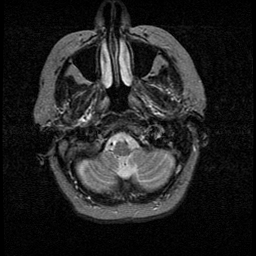

Huntington's Chorea, MR -- Slice #0

[Home][Help][Clinical] Slice 0